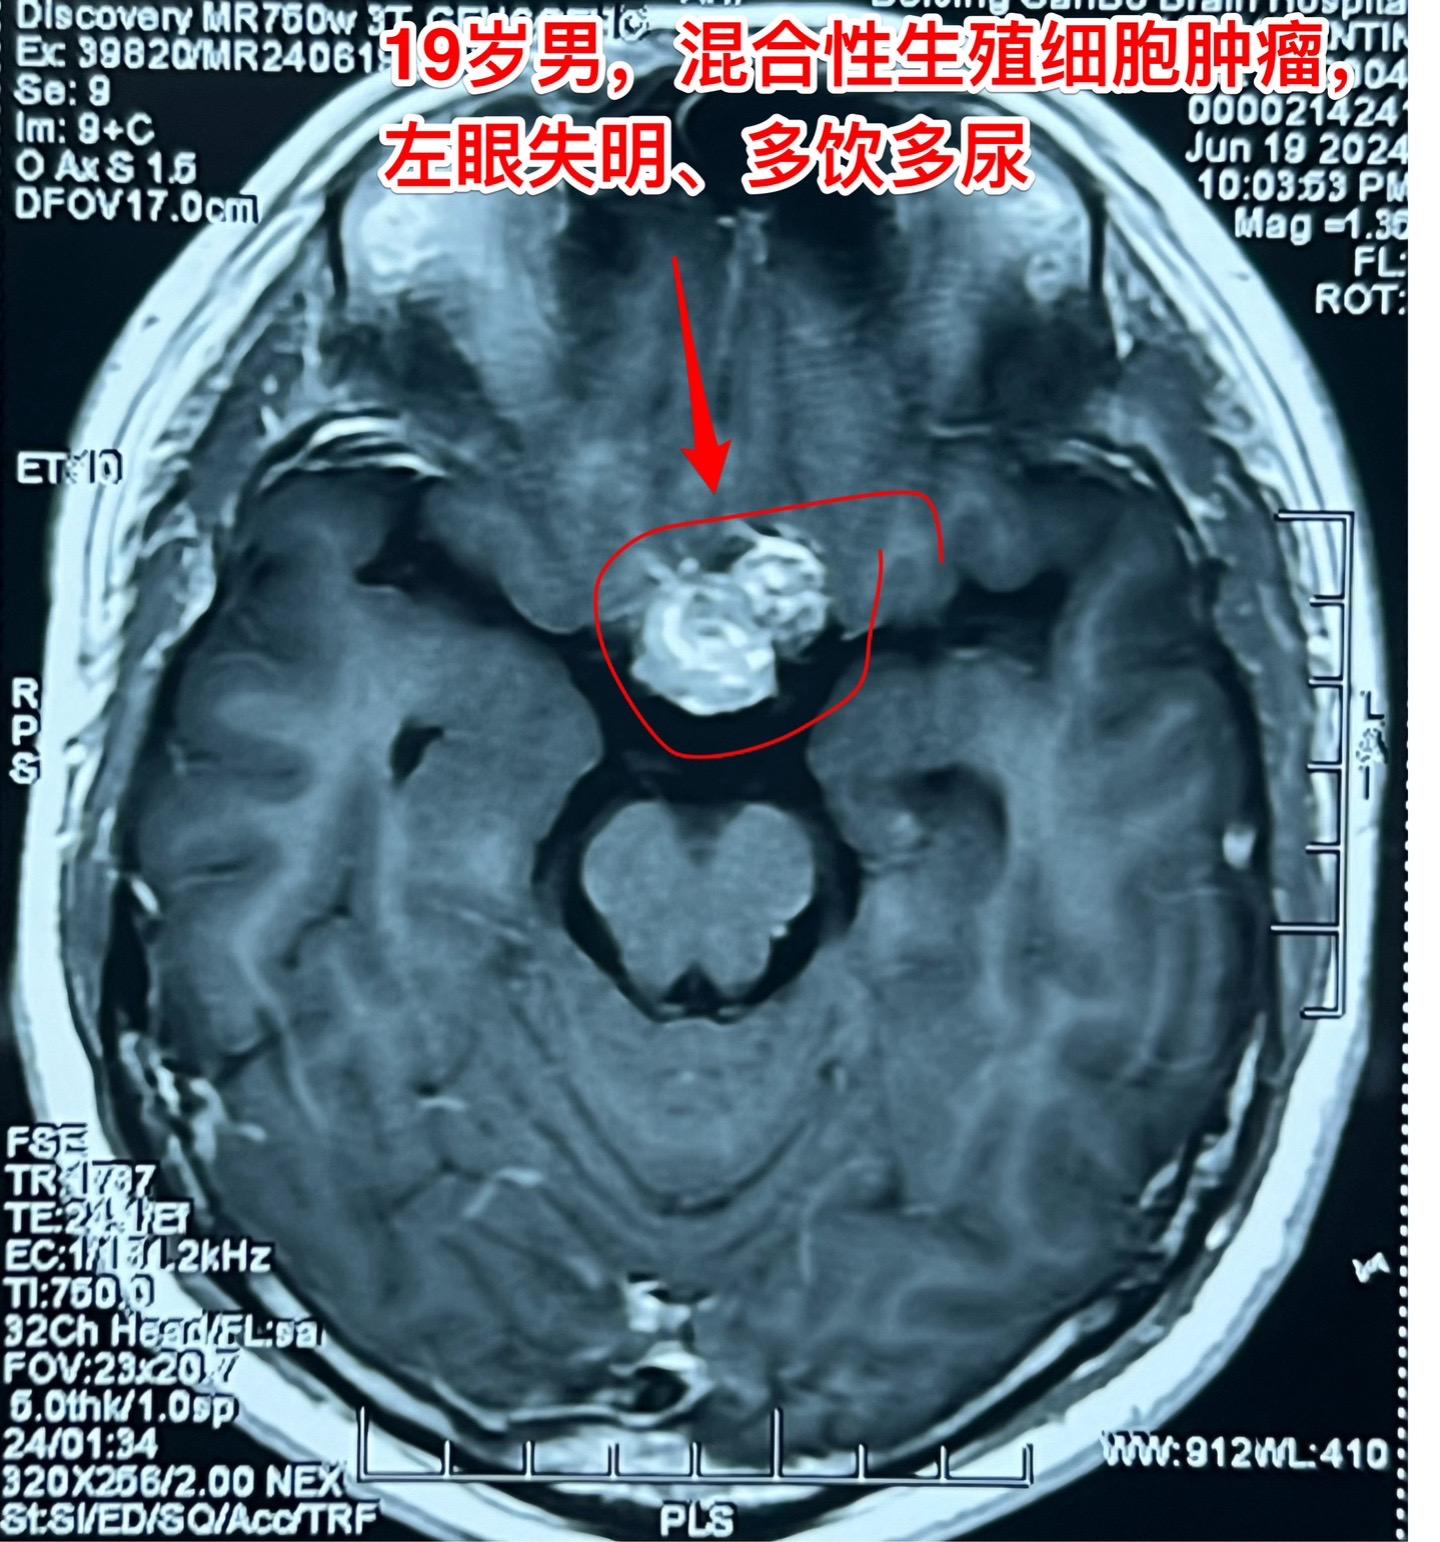

混合性生殖细胞肿瘤复发需要综合治疗。19岁莆田籍男性,三年半前还是新冠疫情期间,就因头痛发现松果体区肿瘤,怀疑是生殖细胞肿瘤,经过伽马刀治疗+化疗,肿瘤消失了,病人能正常上学。 2023年12月病人出现左眼视力下降,多饮多尿症状,复查磁共振显示鞍区肿瘤。取肿瘤活检提示是混合性生殖细胞肿瘤。化疗两个疗程,肿瘤体积稍微变小,停止化疗后肿瘤体积有增大,左眼视力呈恶化趋势,到北京三博来就医时左眼已经失明了。肿瘤的影像学资料见图。化验肿瘤标记物AFP、beta HCG均高于正常,这种情况下首选的是作